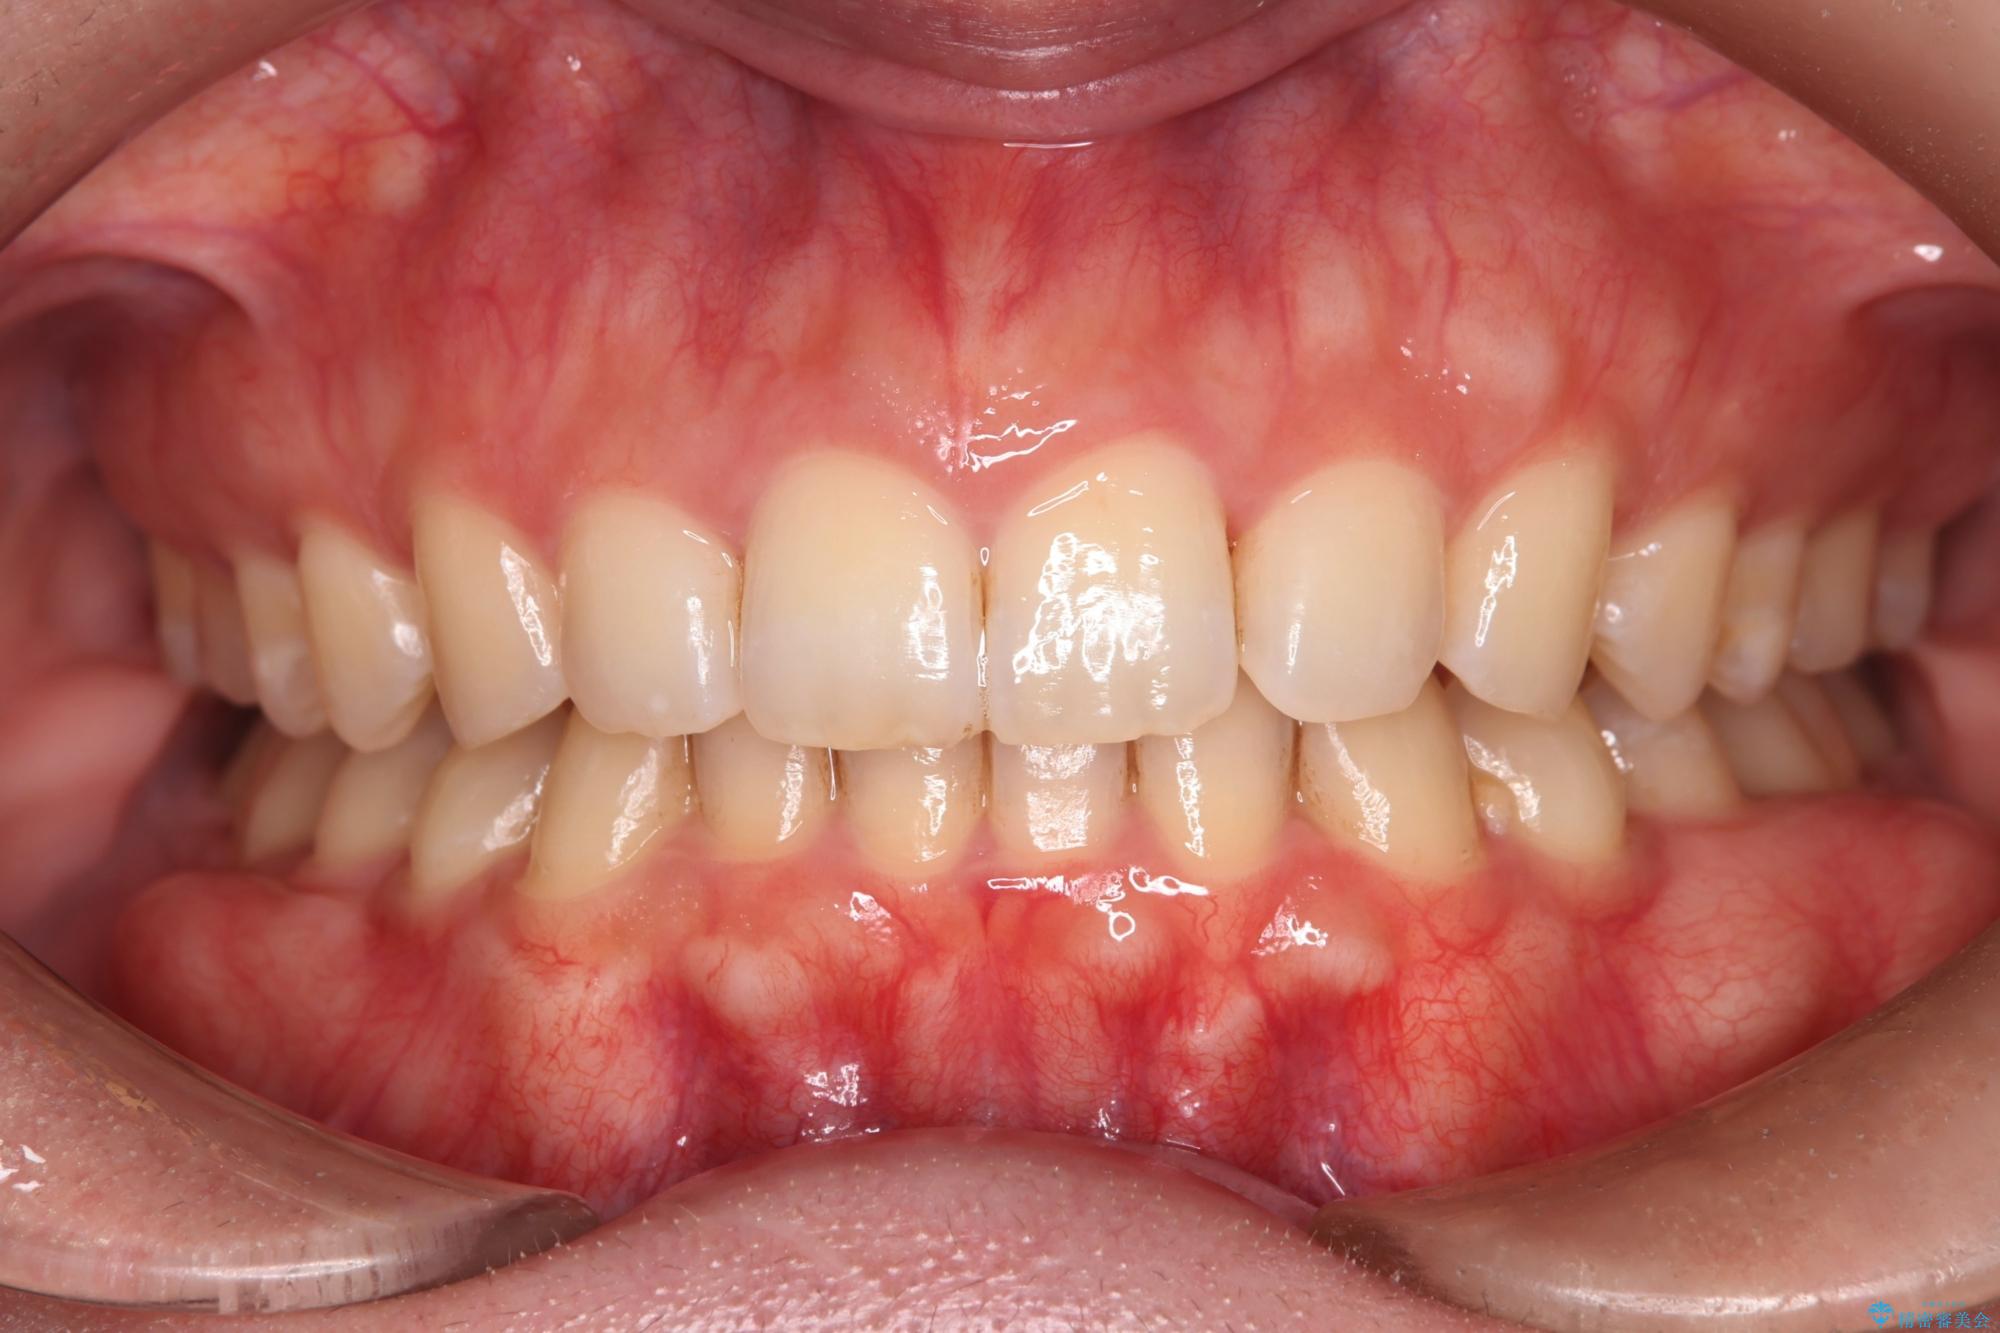

- 下の歯のがたつきを主訴に来院されました。

下の歯のがたつきと右の奥歯の噛みあわせ改善するために治療計画を立てることにしました。

ゴム掛けを頑張っていただいたので、噛みあわせも改善され綺麗な歯並びになりました。